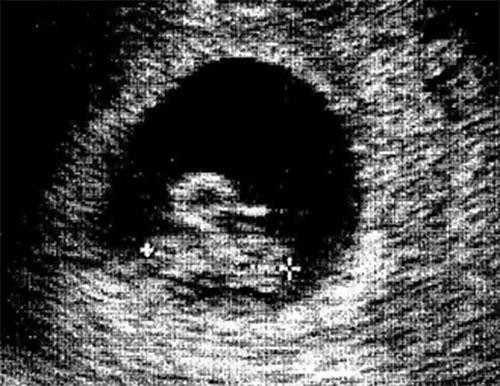

Bebeklerinin bu ilk görüntüsüyle anne-babalar şoke oldu!

Anlamlandırılamayan cisim